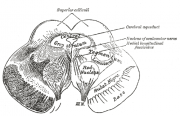

| 2021年7月26日 (一) 18:31 | Gray711.png (文件) |  |

27 KB | 77921020 | Uploaded with SimpleBatchUpload | 1 |